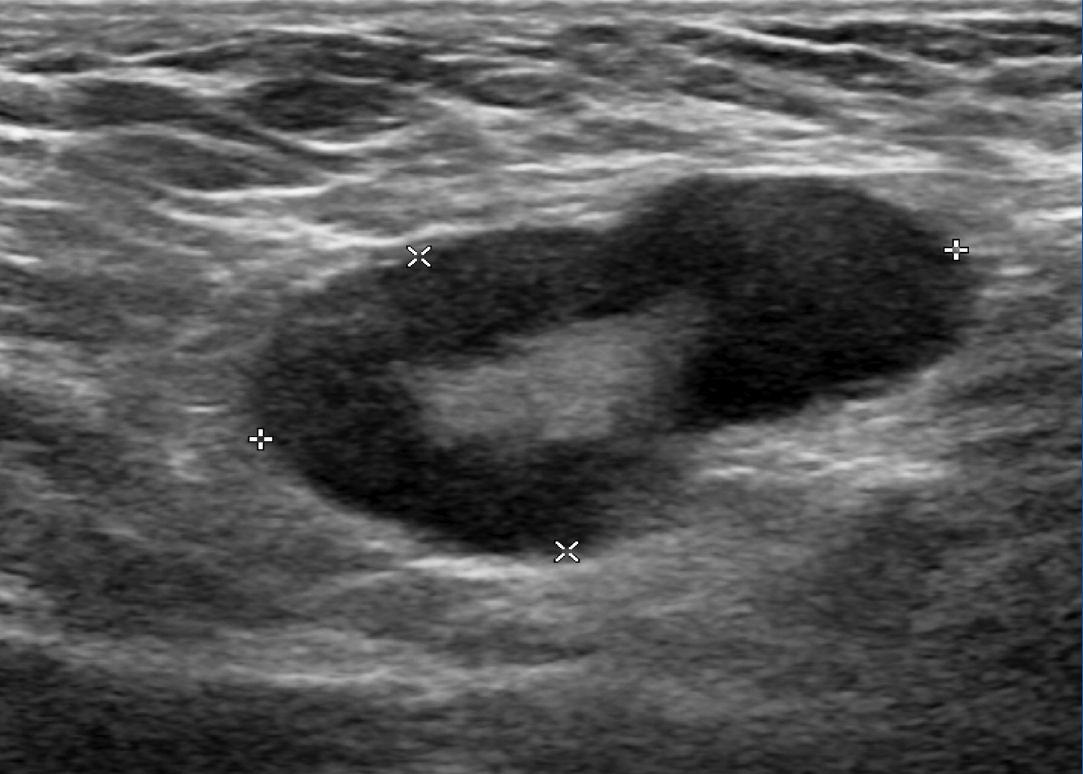

Наиболее удобным, доступным и хорошо изученным методом оценки статуса регионарных лимфатических узлов является УЗИ, при котором возможно оценить форму, контуры и структуру измененных лимфатических узлов. Для метастатических изменений характерна округлая и неправильная форма лимфатического узла (встречаются в 79% наблюдений); рис. 1. Также могут выявляться метастазы в лимфатических узлах с измененным корковым слоем, который проявляется его неравномерным утолщением или выбуханием контура на отдельном участке (рис. 2). Структура метастатически измененных лимфатических узлов многообразна и может быть гипоэхогенной, анэхогенной, гиперэхогенной, гетерогенной, с кальцинатами и даже с включениями жидкостного характера (рис. 3).

Рис. 1. Метастатические изменения регионарных лимфатических узлов в В-режиме: а – измененный надключичный лимфатический узел неправильной формы; б – измененный округлый подмышечный лимфатический узел.

Fig. 1. B-mode ultrasound images of regional lymph node metastases: a – abnormal supraclavicular lymph node with an irregular shape; b – abnormal round axillary lymph node.